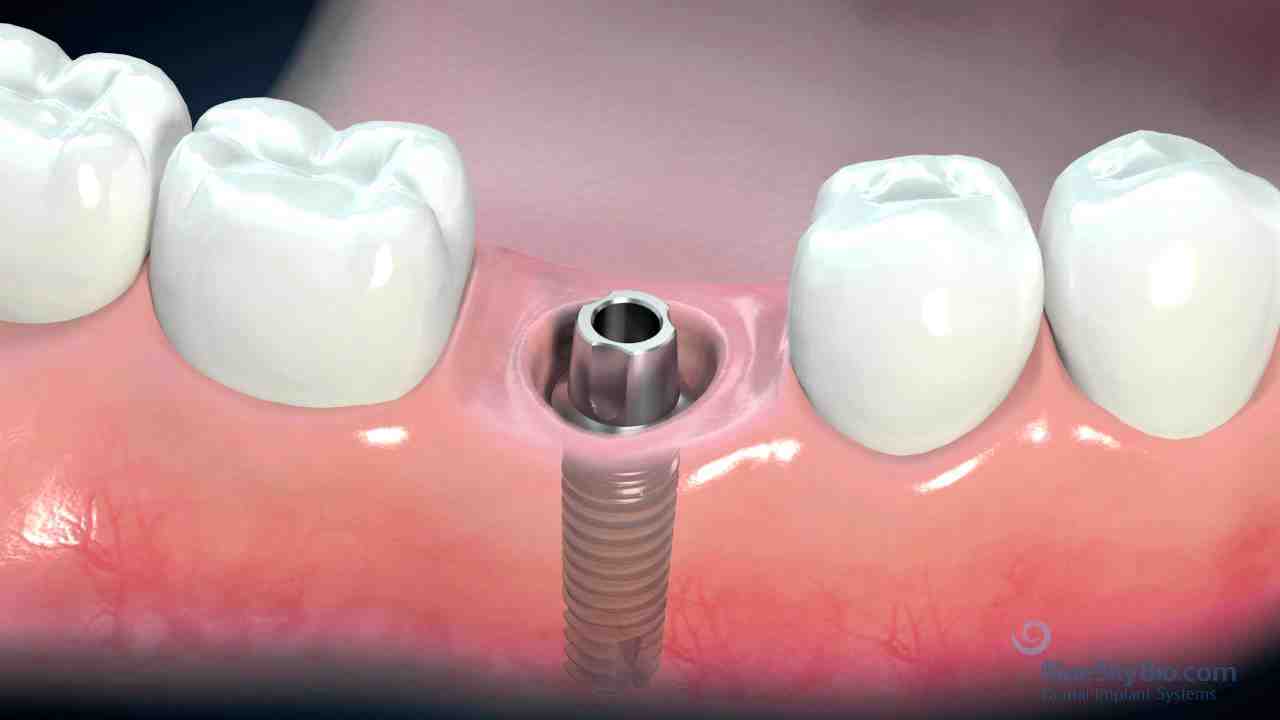

What does a dental implant look like

Because a dental implant is replacing a missing tooth, you have no sensation in the implant itself. Every sensation you have comes from the surrounding rubber tissue. On the same subject : What is a dental implant. This means that the implant does not feel exactly like your natural teeth.

Are Dental Implants Remarkable? No one, not even you, will be able to tell you that you have a dental implant. The implants become feel completely natural in the mouth. Read also : What Does A Tooth Crown Look Like. The dentist matches the color and shape of your other teeth with the implant.